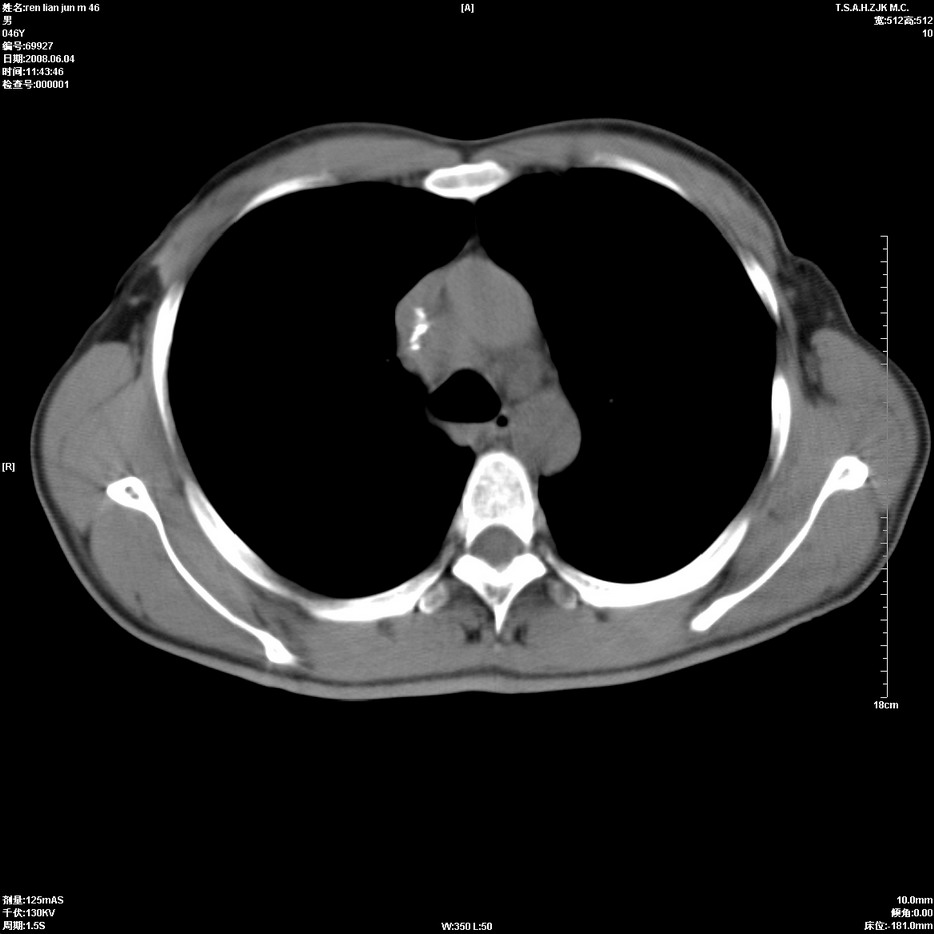

以下是引用qiu999在2008-6-5 17:14:00的发言:[br]考虑右肺中心型肺癌.颅内应做增强检查.

以下是引用形影不离在2008-6-5 19:18:00的发言:[br]右肺中心型肺癌并纵隔及左侧腋窝淋巴结转移,颅内应做增强检查。

以下是引用杀毒软件在2008-6-5 18:33:00的发言:[br]支持考虑右肺中心型肺癌,颅内病变是不是转移,不好说